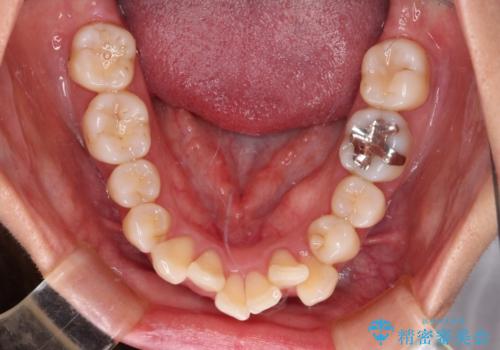

- 八重歯と上の前歯が出っ歯になっていることを気にして来院された患者様です。

横から見た際の口元の飛び出した印象も改善したいとのことで、上下左右の第一小臼歯4本を抜歯し、ワイヤー装置にて抜歯矯正を行うこととしました。

前歯の変色している歯は、神経組織が壊死していたため、矯正治療前に根管治療を実施し、矯正治療後にオールセラミッククラウンにて補綴治療を行うこととしました。